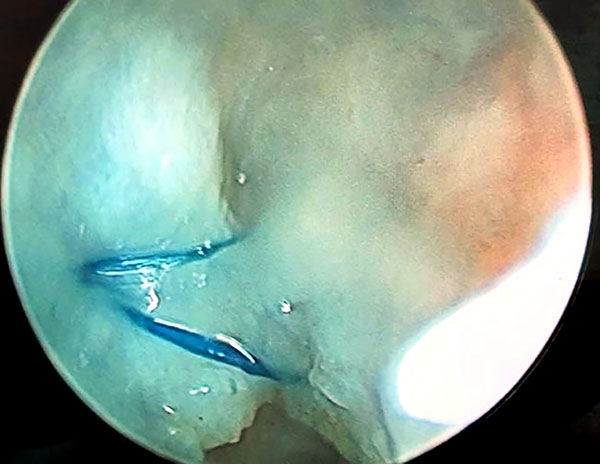

Se realiza visión por portal 6r y se pasa la aguja por la cápsula y uno de los sectores dañados del ligamento escafolunar hacia la articulación mediocarpiana donde se rescata la sutura y se retira por el portal MCR con visión MCU. Se repite este paso con otra aguja paralela a la primera que atraviese la cápsula y la otra parte del ligamento escafolunar dañada, y se rescata la sutura por articulación medio carpiana. Las 2 suturas rescatadas por mediocarpiano se anudan de forma simple, y se realiza el deslizamiento de los extremos de las suturas proximales con visión MCU, consiguiendo que el nudo quede anclado por mediocarpiano en el lig. Escafolunar (figs. 5 a 10).

Figuras 1 a 10: Muestran el ingreso de las agujas desde el portal radiocarpiano al mediocarpiano y el retiro de los hilos por el portal MCR con el nudo anclado en espacio mediocarpiano.

Luego realizamos una incisión de 5 mm entre los cabos de las suturas proximales, divulsionamos hasta cápsula y con visión 6r, realizamos un nudo simple de ambos extremos del hilo consiguiendo así la plicatura de la capsula dorsal (figs. 11 y 12).

Figuras 11 y 12: Muestran los hilos por portal radiocarpiano antes del anudado capsular y luego del anudado con la plicatura capsular.